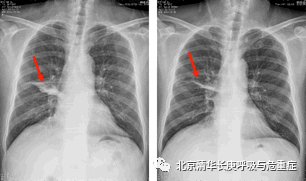

1个月后,患者症状基本消失,复查胸片显示肺部病变较前明显吸收好转(图5)。出院后继续口服泊沙康唑5ml(200mg),每日四次,定期门诊随诊。

图5入院时胸片显示右肺病变;治疗1个月后复查胸片显示右肺病变明显吸收好转。